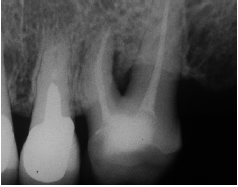

Al momento del examen, 10 (90.9%) EC estaban en función en 10 pacientes. Un molar 26, restaurado con EC, se perdió por enfermedad periodontal después de 12 años y 9 meses en función. Ninguna restauración se desprendió, no hubo recidiva de caries y al examen radiográfico no se observaron lesiones patológicas en los 10 DPET en función (Figs. 1a,1d; 2c; 3c,3d; 4c).

Radiografía final del tratamiento endodóntico

Control radiográfico a los 18 años